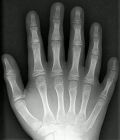

六指症一目了然,孩子出生就被發現有多餘的手指,畸形類型和嚴重程度多樣,有的僅以狹小的包裹著血管神經的皮蒂與正常手指相連;有的具有指甲、骨關節、肌腱和血管神經束,並具有一定的手指活動和感覺功能,造成手術取捨方面的困難;甚至有的畸形嚴重如“蟹鉗樣”,手指發育差,手指細小、偏曲,嚴重影響手部外觀和功能。除了生理上的影響外,患兒和家長往往還有心理上的問題,心理上的顧忌會影響到孩子的心理發育,影響學習和社會生活,甚至影響到以後的就業、工作和婚姻。

X線或CT檢查可進一步了解多指的骨與關節情況。診斷

本病根據病史及體格檢查即可明確診斷,輔助檢查主要是X線攝片明確其類型及骨骼關節生長情況,為治療方案的選擇提供依據,對於複雜疑難病例,也可行螺鏇CT檢查,三維立體重建,進一步明確畸形類型和程度。治療